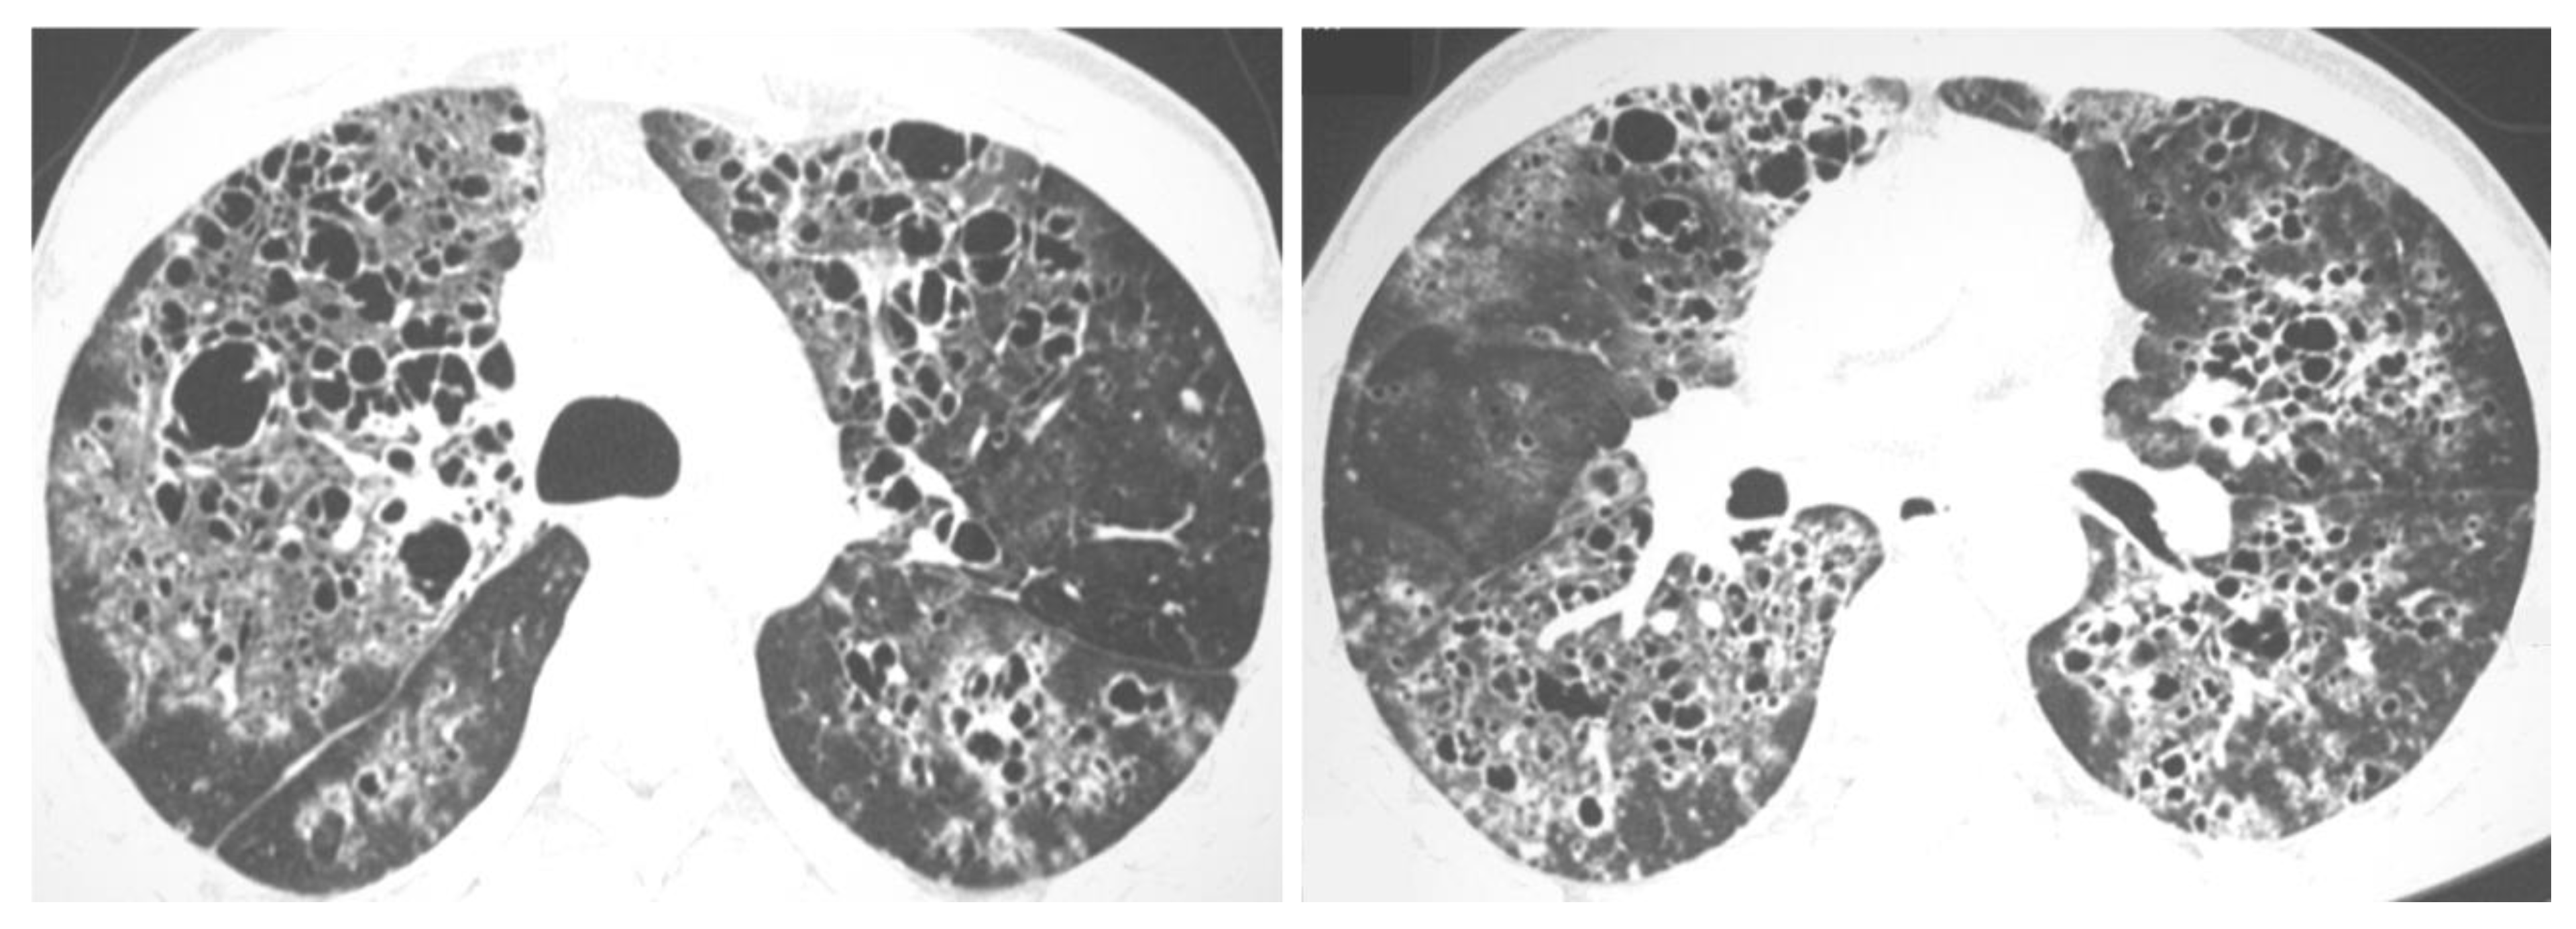

2.3. Chronic Cavitating Disease

- Barreto, M.M.; Marchiori, E.; Amorim, V.B.; Zanetti, G.; Takayassu, T.C.; Escuissato, D.L.; Souza, A.S.; Rodrigues, R.S. Thoracic paracoccidioidomycosis: Radiographic and CT findings [published correction appears in Radiographics. Radiographics 2012, 32, 71–84. [Google Scholar] [CrossRef] [PubMed]

- Marchiori, E.; Valiante, P.M.; Mano, C.M.; Zanetti, G.; Escuissato, D.L.; Souza, A.S.; Capone, D. Paracoccidioidomycosis: High-resolution computed tomography-pathologic correlation. Eur. J. Radiol. 2011, 77, 80–84. [Google Scholar] [CrossRef]